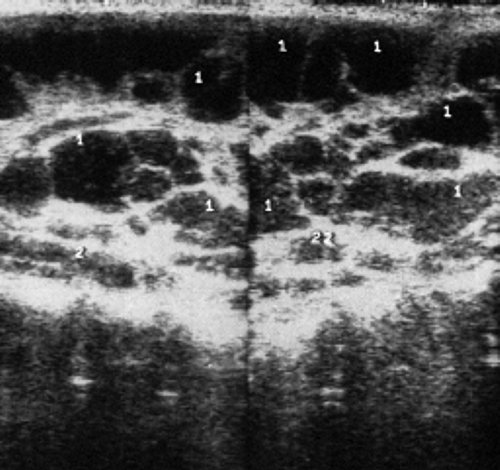

УЗИ лимфоузлов при лимфоме Ходжкина

Раздел: Образы вокруг